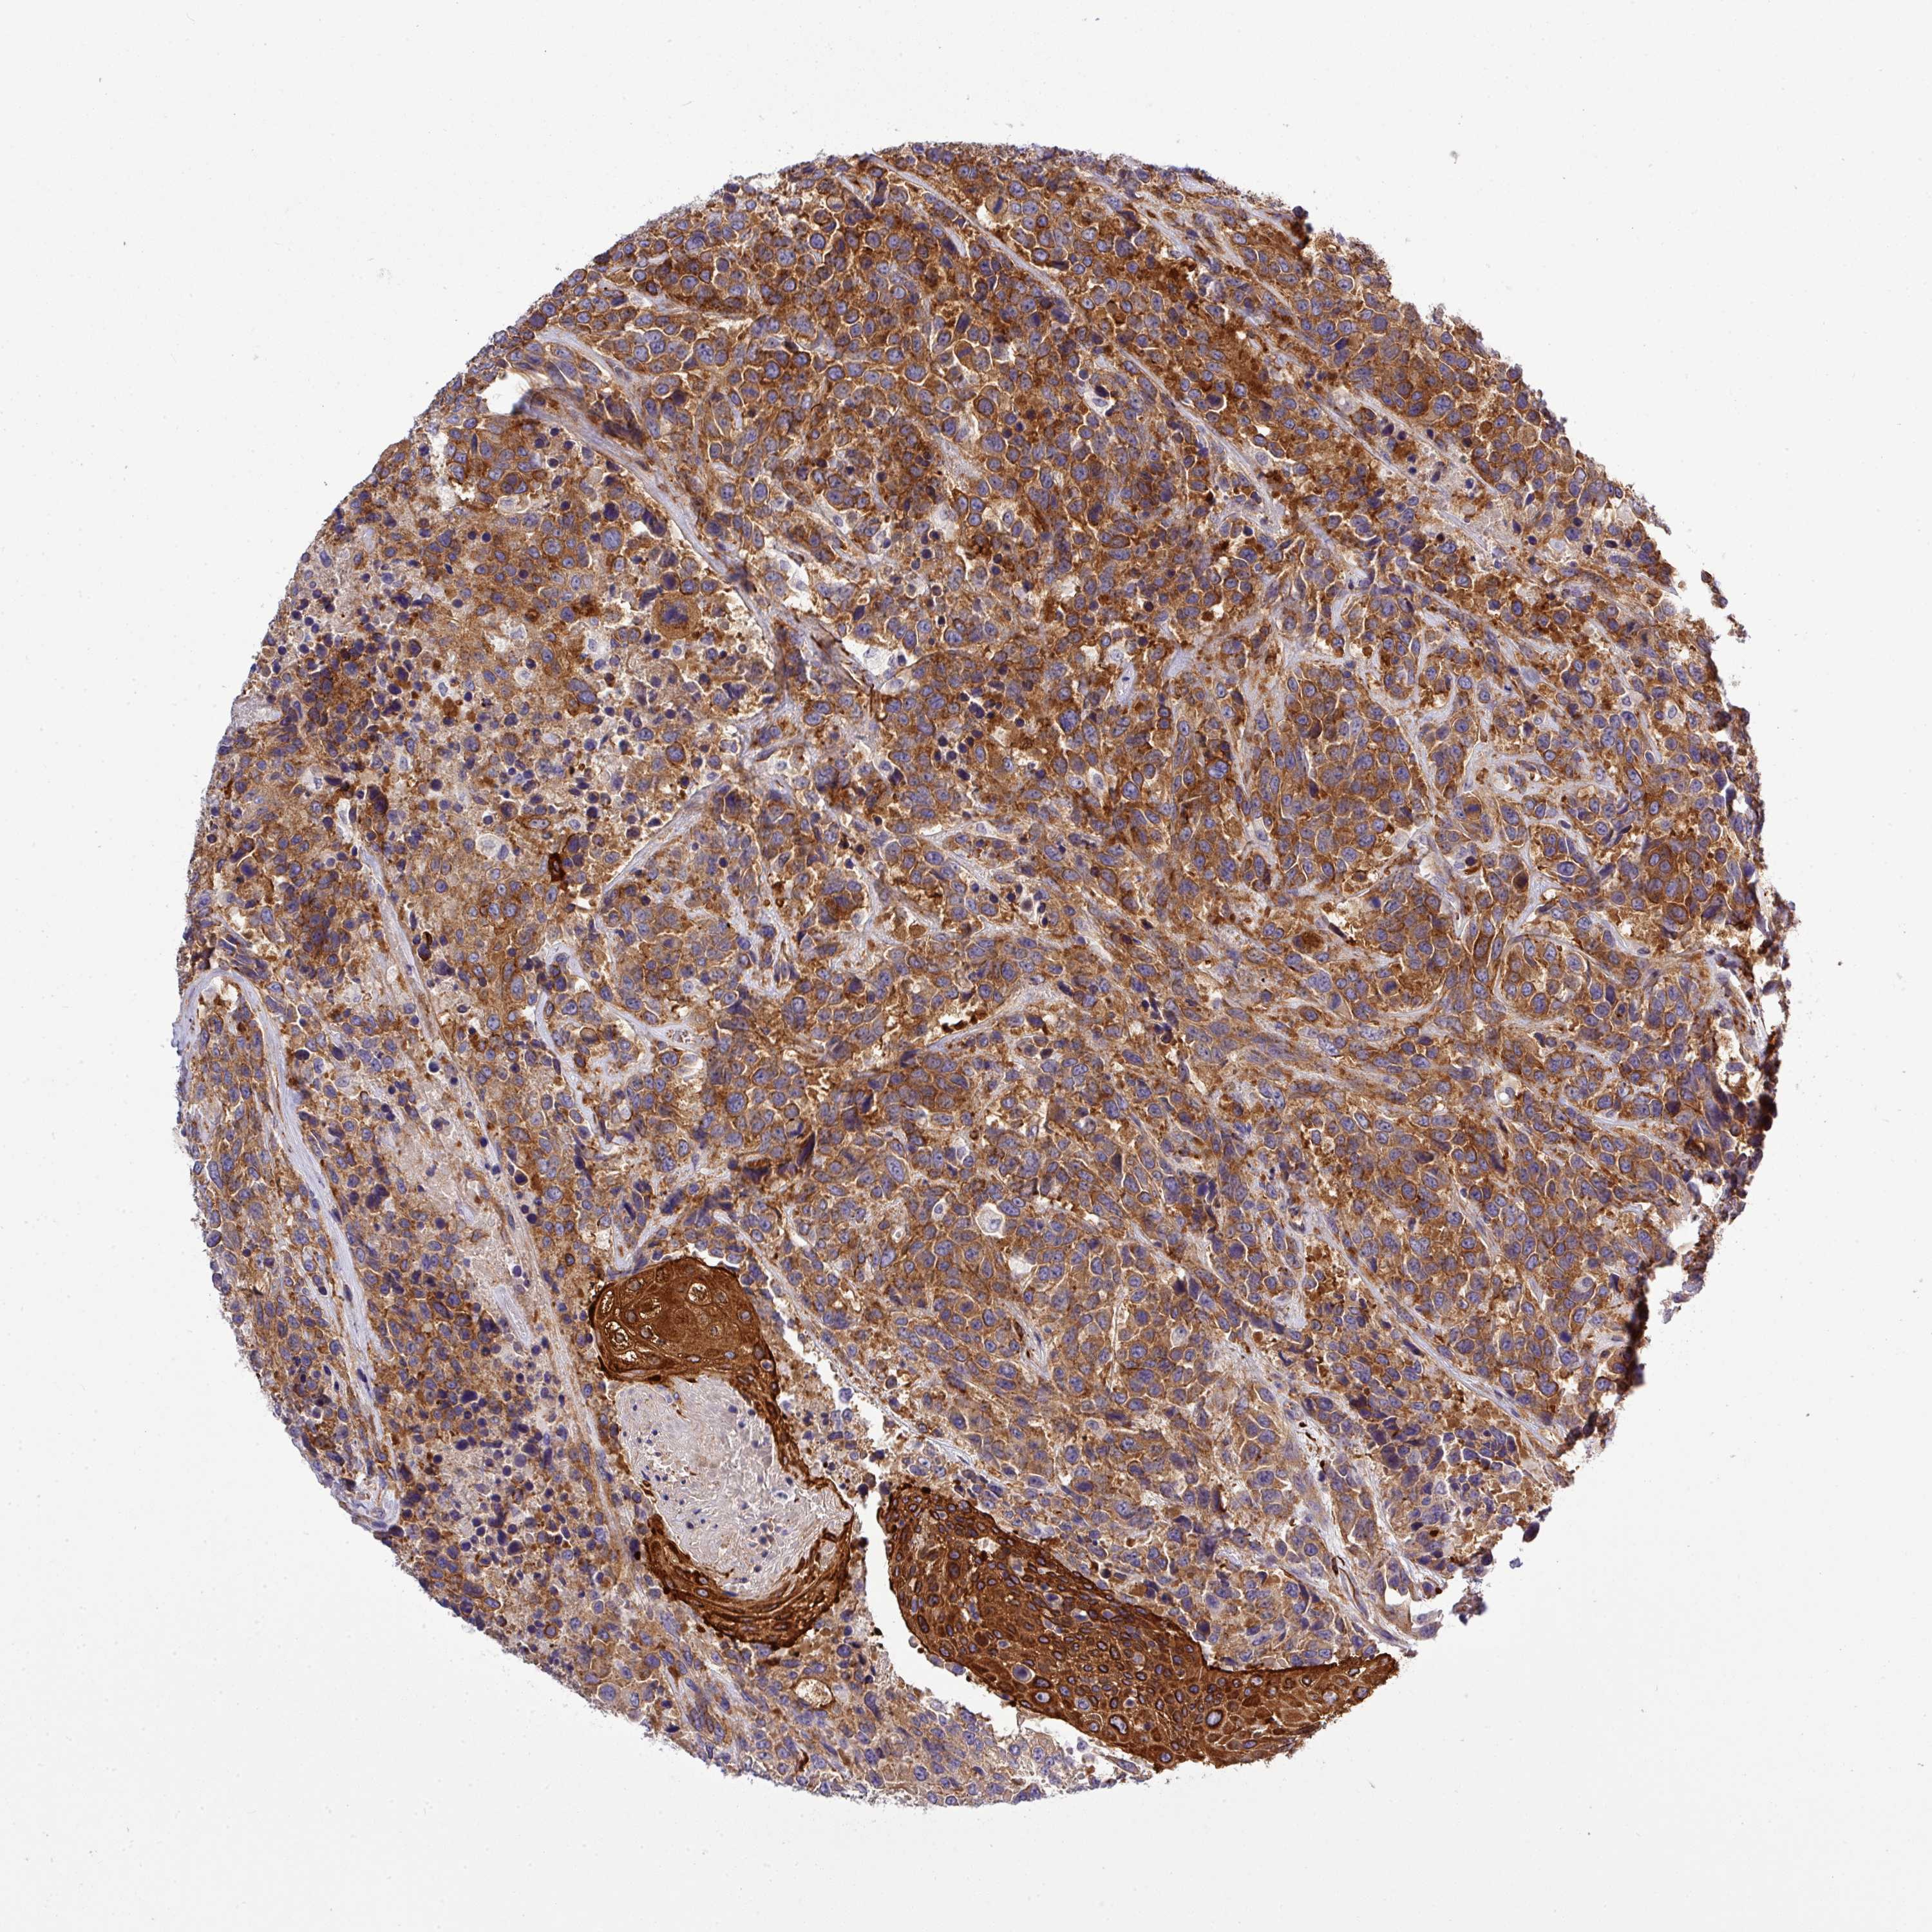

UROTHELIAL CANCER - Protein expressioni

A mouse-over function shows sample information and annotation data. Click on an image to view it in a full screen mode. Samples can be filtered based on level of antibody staining by selecting one or several of the following categories: high, medium, low and not detected. The assay and annotation is described here.

Note that samples used for immunohistochemistry by the Human Protein Atlas do not correspond to samples in the TCGA dataset.

Antibody stainingi

Antibody staining in the annotated cell types in the current human tissue is reported as not detected, low, medium, or high, based on conventional immunohistochemistry profiling in selected tissues. This score is based on the combination of the staining intensity and fraction of stained cells.

Each image is clickable and will lead to virtual microscopy that enables deeper exploration of all samples and also displays staining intensity scores, fraction scores and subcellular localization as well as patient and tissue information for each sample.

Antibody HPA041551

Antibody CAB009733

Urothelial carcinoma, Low grade

Urothelial carcinoma, High grade